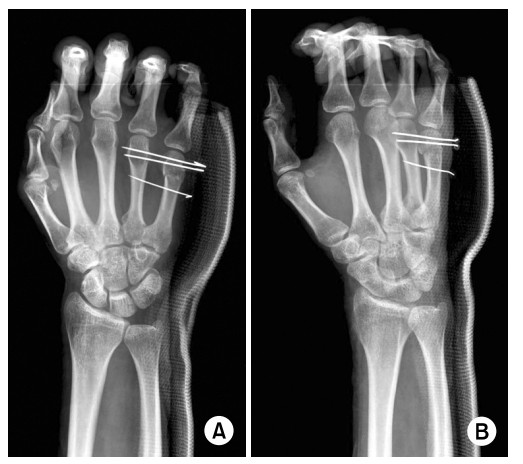

3주 전 오른손 제5수지(오른손 새끼손가락쪽) 중수골 경부골절 진단을 받고 k-강선 4개를 횡으로 삽입하는 수술을 하였습니다.

(사진은 제 사진이 아니며 인터넷 검색해서 관련 논문들 중 제 사진과 가장 유사한 것을 가져왔습니다)

1. 현재 주먹을 쥘 때 새끼손가락이 끝까지 쥐어지지 않습니다. 왼손으로 해보니 주먹을 꽉 쥐게되면 제5수지 중수골이 주먹 안쪽으로 말리면서 힘을 주게 되는데, 현재 사진처럼 제5수지 중수골과 제4수지 중수골이 강선으로 고정되어 있어서 주먹이 끝까지 안쥐어지는게 맞나요?